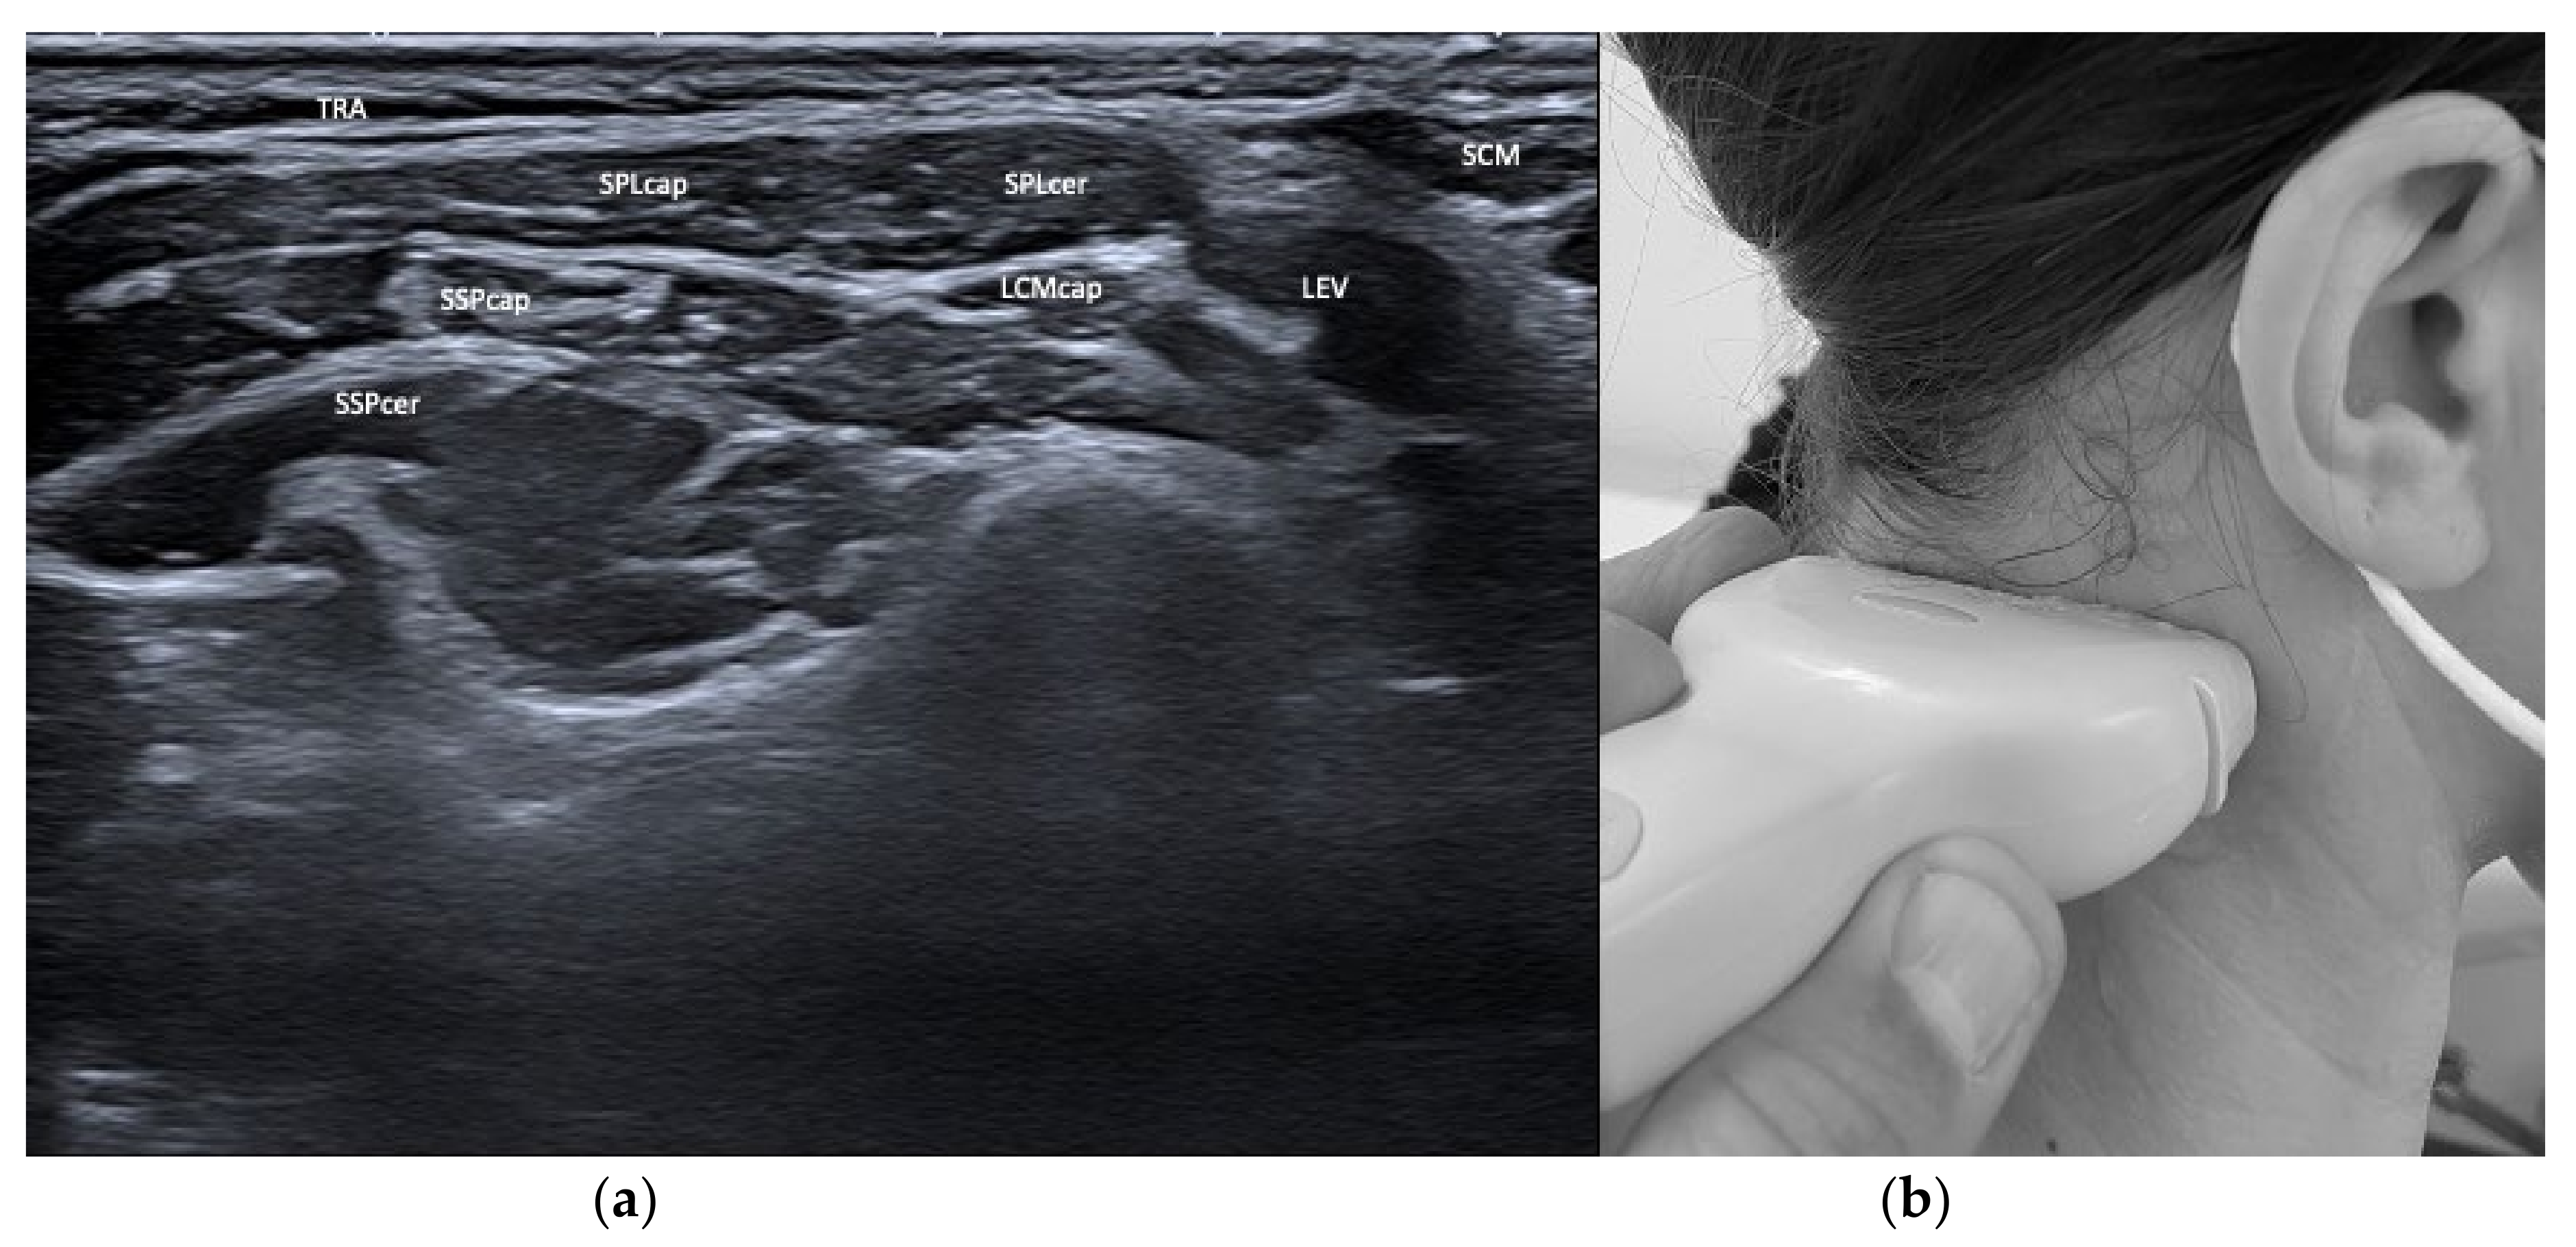

| Semispinalis capitis (SSPcap) | Extension of head | + | + | SPLcap, OCI | Strongest extensor muscle of head and neck |

| Semispinalis cervicis (SSPcer) | Extension of neck | + | + | SPLcer, TRA | |

| Splenius capitis (SPLcap) | Ipsiversion of head | ++ | ++ | major occipital nerve, SPLcap/cer, LSMcap, OCI | Prominent reduction in bulk from repeated injections possible |

| Splenius cervicis (SPLcer) | Ipsiversion of neck | +++ | ++ | LEV, TRA, Longissimus cervicis | Relevant for full turn of the neck |

| Longissimus capitis (LCM) | Ipsiversion of head and neck | +++ | ++ | SPLcap, SSPcap | Obligatory USG |

| Trapezius (TRA) | Extension of neck | + | + | LEV, Supraspinatus | |

| Levator scapulae (LEV) | Lift of scapula | + | + | SPLcer, TRA | |